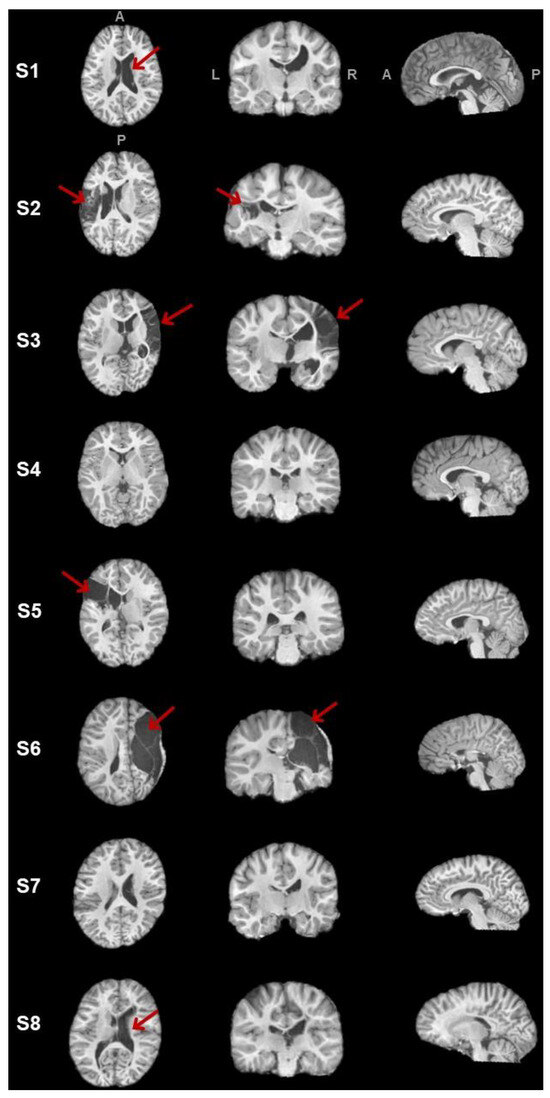

| Sex | Age | Lesion Side | Etiology | MACS | |

|---|---|---|---|---|---|

| S1 | M | 13 y, 10 m | Right | Pre- or perinatal stroke (undefined) | I |

| S2 | M | 12 y, 5 m | Left | Perinatal stroke | III |

| S3 | F | 8 y, 9 m | Right | Prenatal stroke | II |

| S4 | M | 9 y, 3 m | Right | Unknown | I |

| S5 | F | 11 y, 6 m | Left | Periventricular leukomalacia | II |

| S6 | F | 11 y, 4 m | Right | Prenatal stroke | III |

| S7 | M | 13 y, 3 m | Right | Prenatal stroke | I |

| S8 | F | 11 y, 3 m | Right | Prenatal stroke | II |